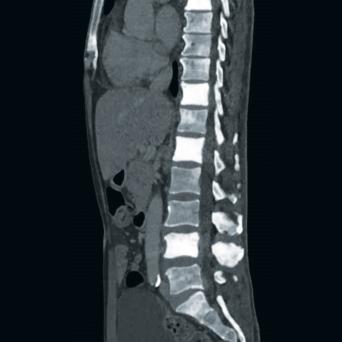

L’image

du jour

Illustration.